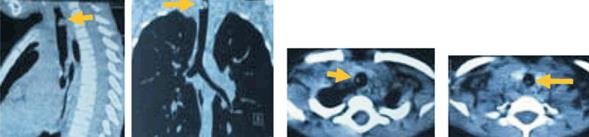

Se solicita tomografía de cuello y tórax con reconstrucción tridimensional que muestra lesión groseramente redondeada de aproximadamente 9 por 4 mm en el sector basal de la epiglotis por cara laríngea; imagen protruyente vegetante de 10 por 7 mm asentada en la pared posterior y lateral derecha de la tráquea a unos 27 mm de la epiglotis, y otra lesión ligeramente elevada de 3 mm aproximadamente a unos 15 mm de la carina (Figura 3), se señalan con flechas las alteraciones descritas.